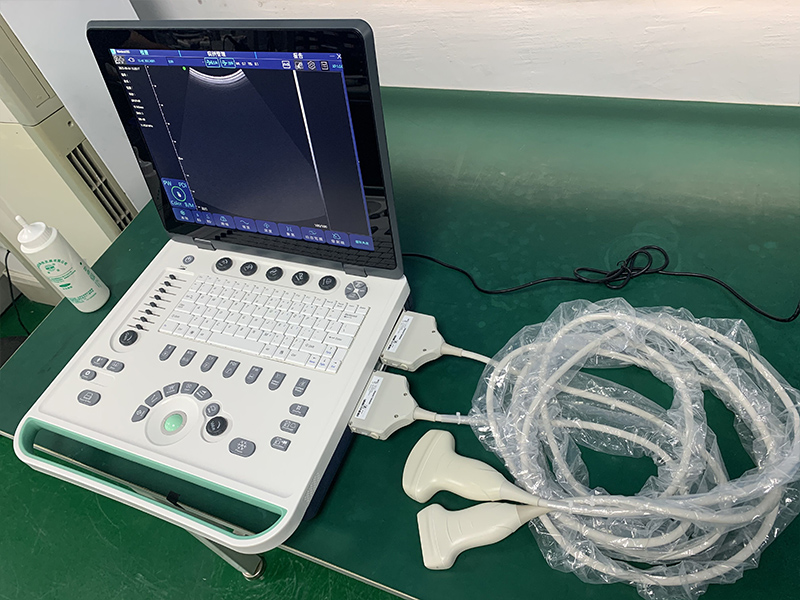

技术参数:

- 屏幕尺寸:15英寸

- 探头类型:凸阵、线阵、相控阵、微凸、腔内、直肠

- 探头接口:2个

- 主机尺寸:L362×W340×H50mm

- 主机重量:4Kg

标准配置:

主机 1台

凸阵探头 1个

可选配件:

线阵、相控阵、微凸、腔内、直肠等探头,探头穿刺架,平板,推车,外置电池,远程会诊系统